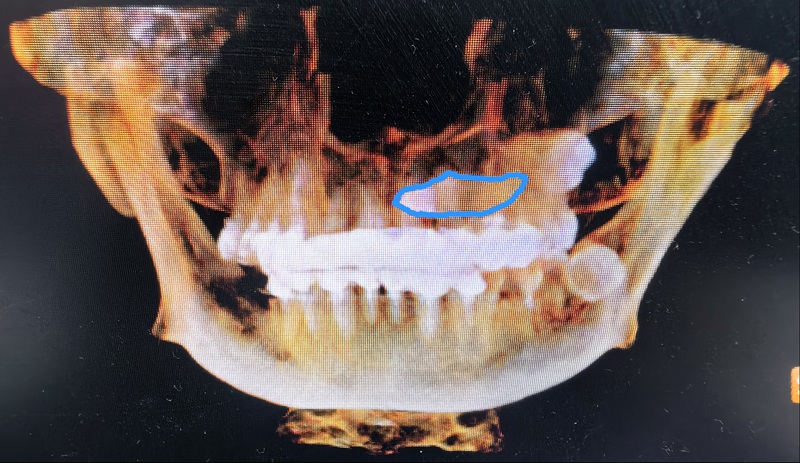

術前:尖牙橫行貫穿埋伏于左上頜骨內,牙冠位于上腭,牙根位于鼻根側下方。

劉弦醫生仔細查看口腔錐形束CT影像,發現這顆左上頜埋伏尖牙堪稱“定時炸彈”——碩大的牙根死死壓迫鄰牙,稍有拖延便會連累鄰牙不保。更棘手的是,這顆牙前臨鼻腔、后靠上頜竇,周圍纏繞著鼻腭神經血管束,拔除時稍有偏差,牙體就可能墜入鼻腔或上頜竇;面對謝女士“希望門診局麻下拔牙”的請求,這個手術難度堪比在精密儀器上“穿針引線”。

術后:鄰牙、神經、鼻腔及上頜竇粘膜均無損傷。